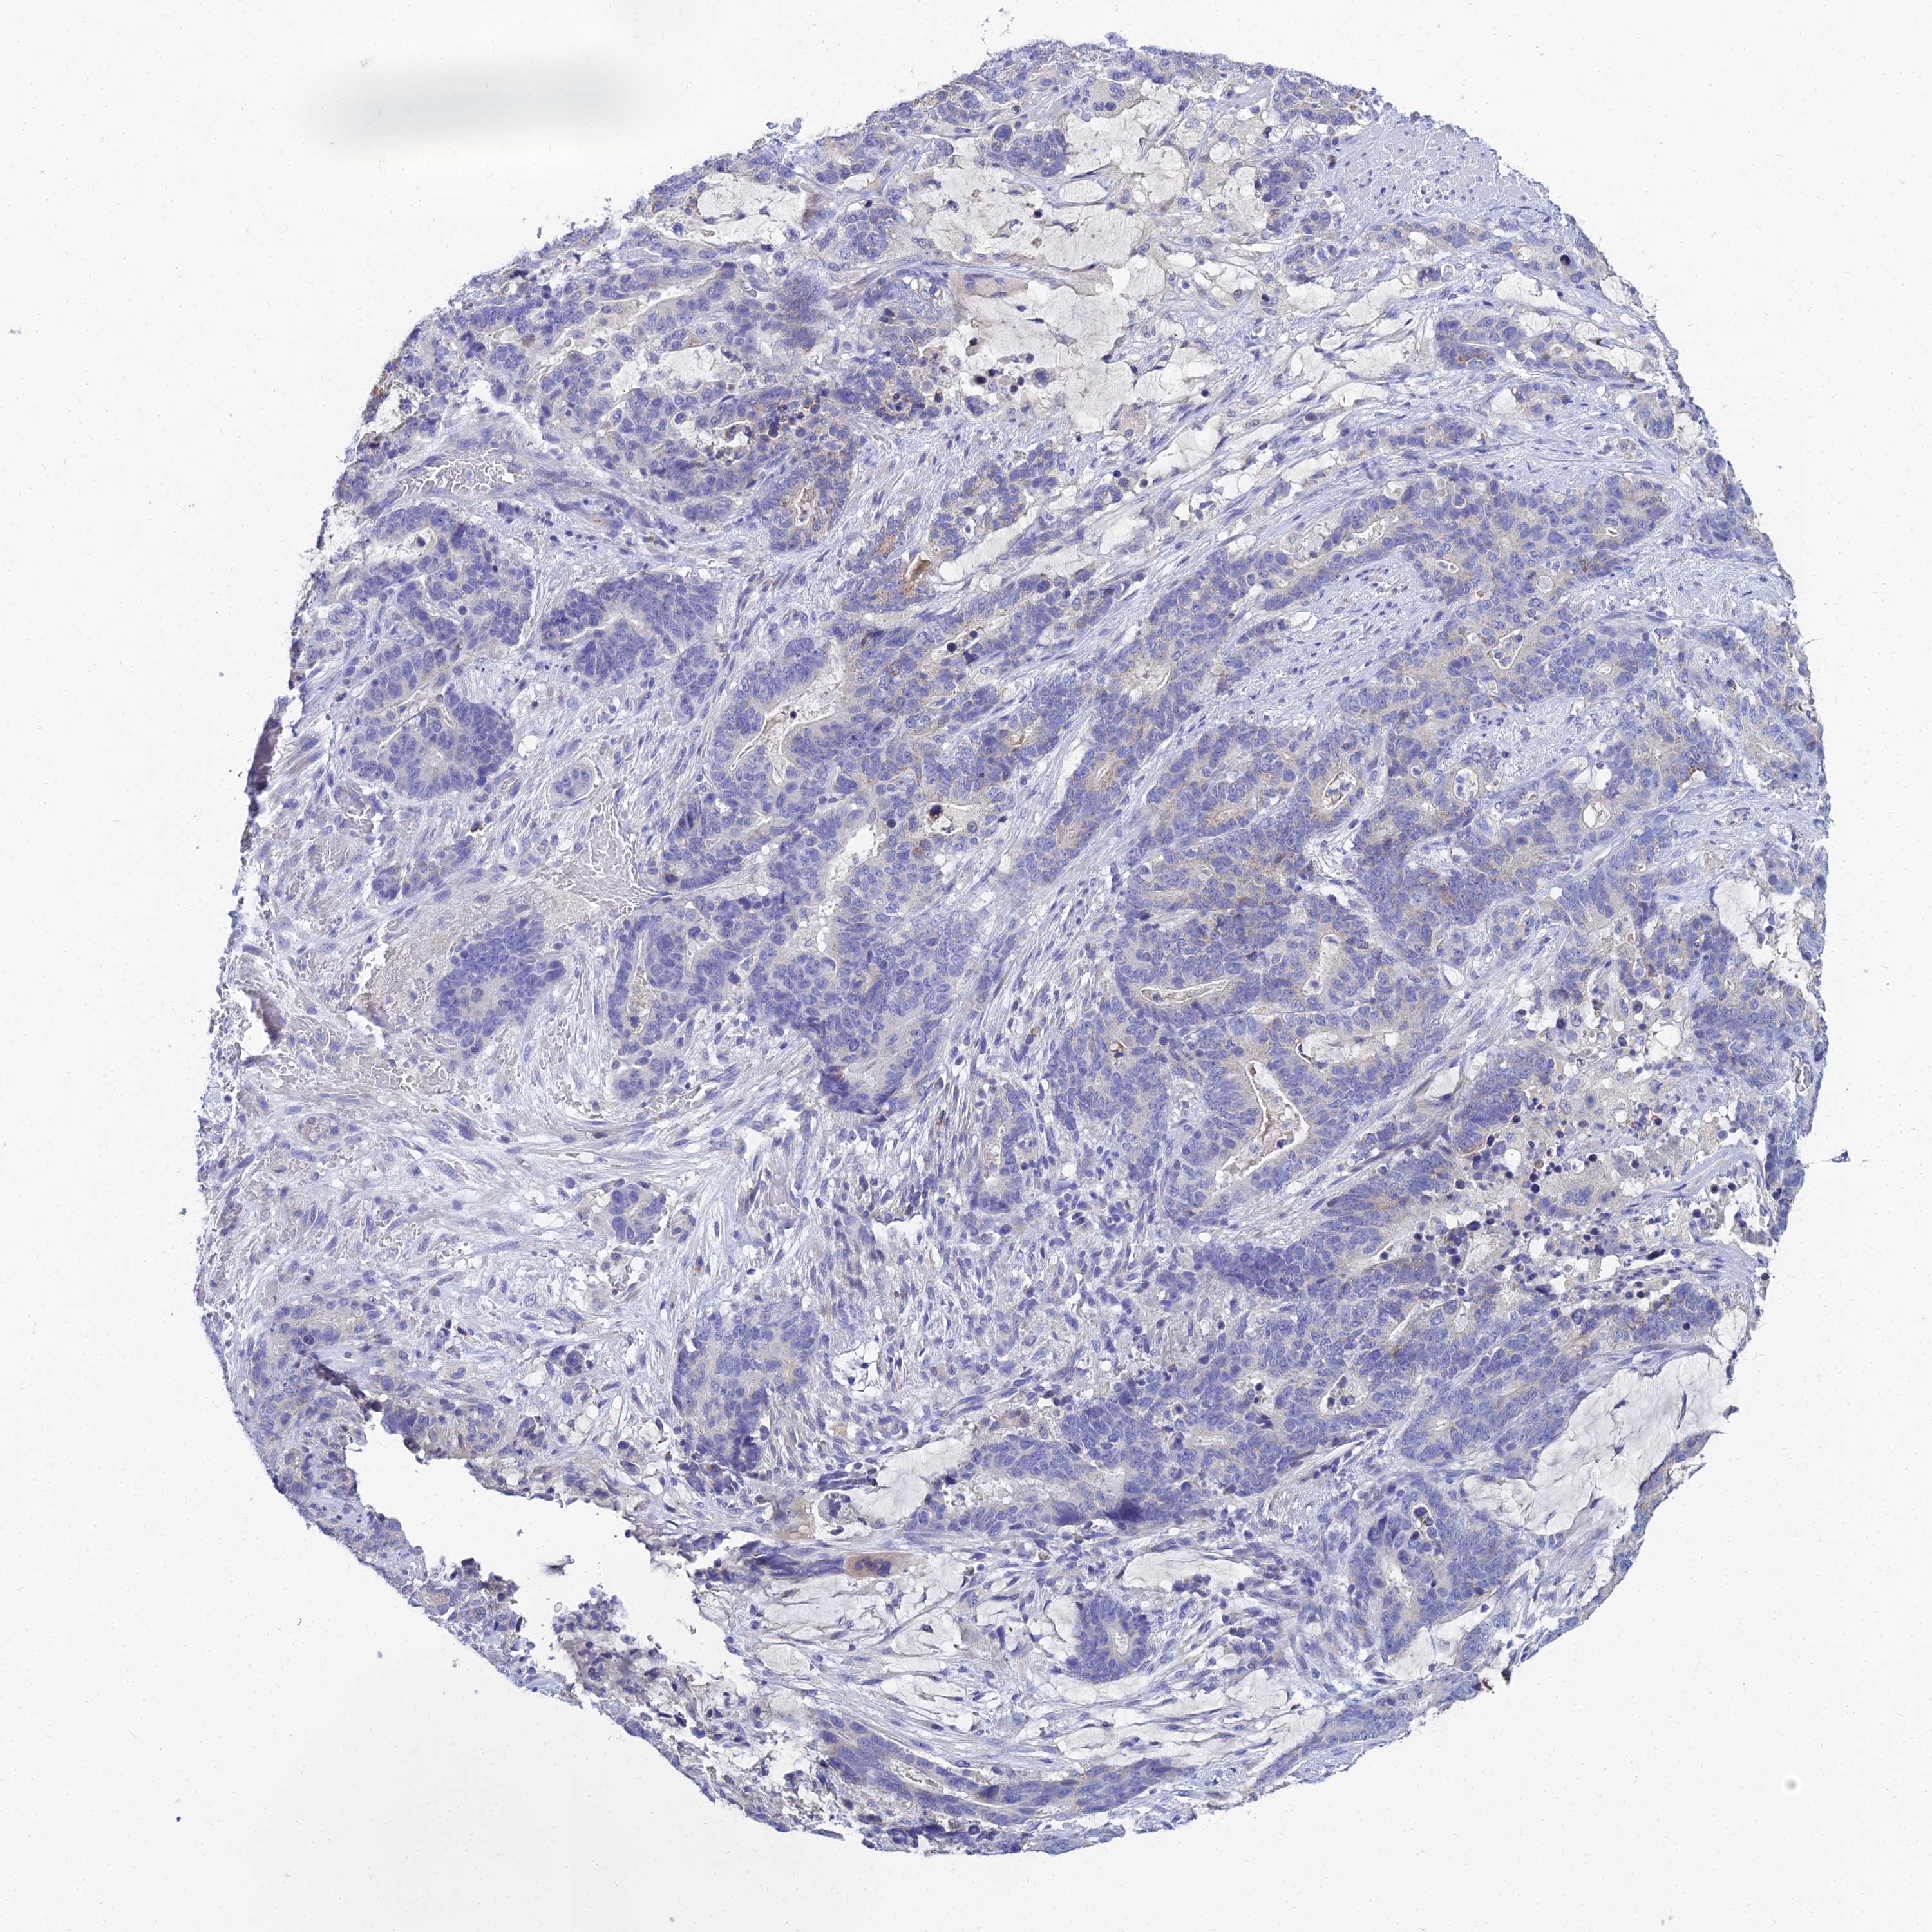

STOMACH CANCER - Protein expressioni

A mouse-over function shows sample information and annotation data. Click on an image to view it in a full screen mode. Samples can be filtered based on level of antibody staining by selecting one or several of the following categories: high, medium, low and not detected. The assay and annotation is described here.

Antibody stainingi

Antibody staining in the annotated cell types in the current human tissue is reported as not detected, low, medium, or high, based on conventional immunohistochemistry profiling in selected tissues. This score is based on the combination of the staining intensity and fraction of stained cells.

Each image is clickable and will lead to virtual microscopy that enables deeper exploration of all samples and also displays staining intensity scores, fraction scores and subcellular localization as well as patient and tissue information for each sample.

Antibody HPA044572

Antibody HPA056798

Antibody CAB016733

Antibody CAB034368

Staining

High

Medium

Low

Not detected

Intensity

Strong

Moderate

Weak

Negative

Quantity

>75%

75%-25%

<25%

None

Location

Nuclear

Cytoplasmic/membranous

Cytoplasmic/membranous,nuclear

Adenocarcinoma, NOS